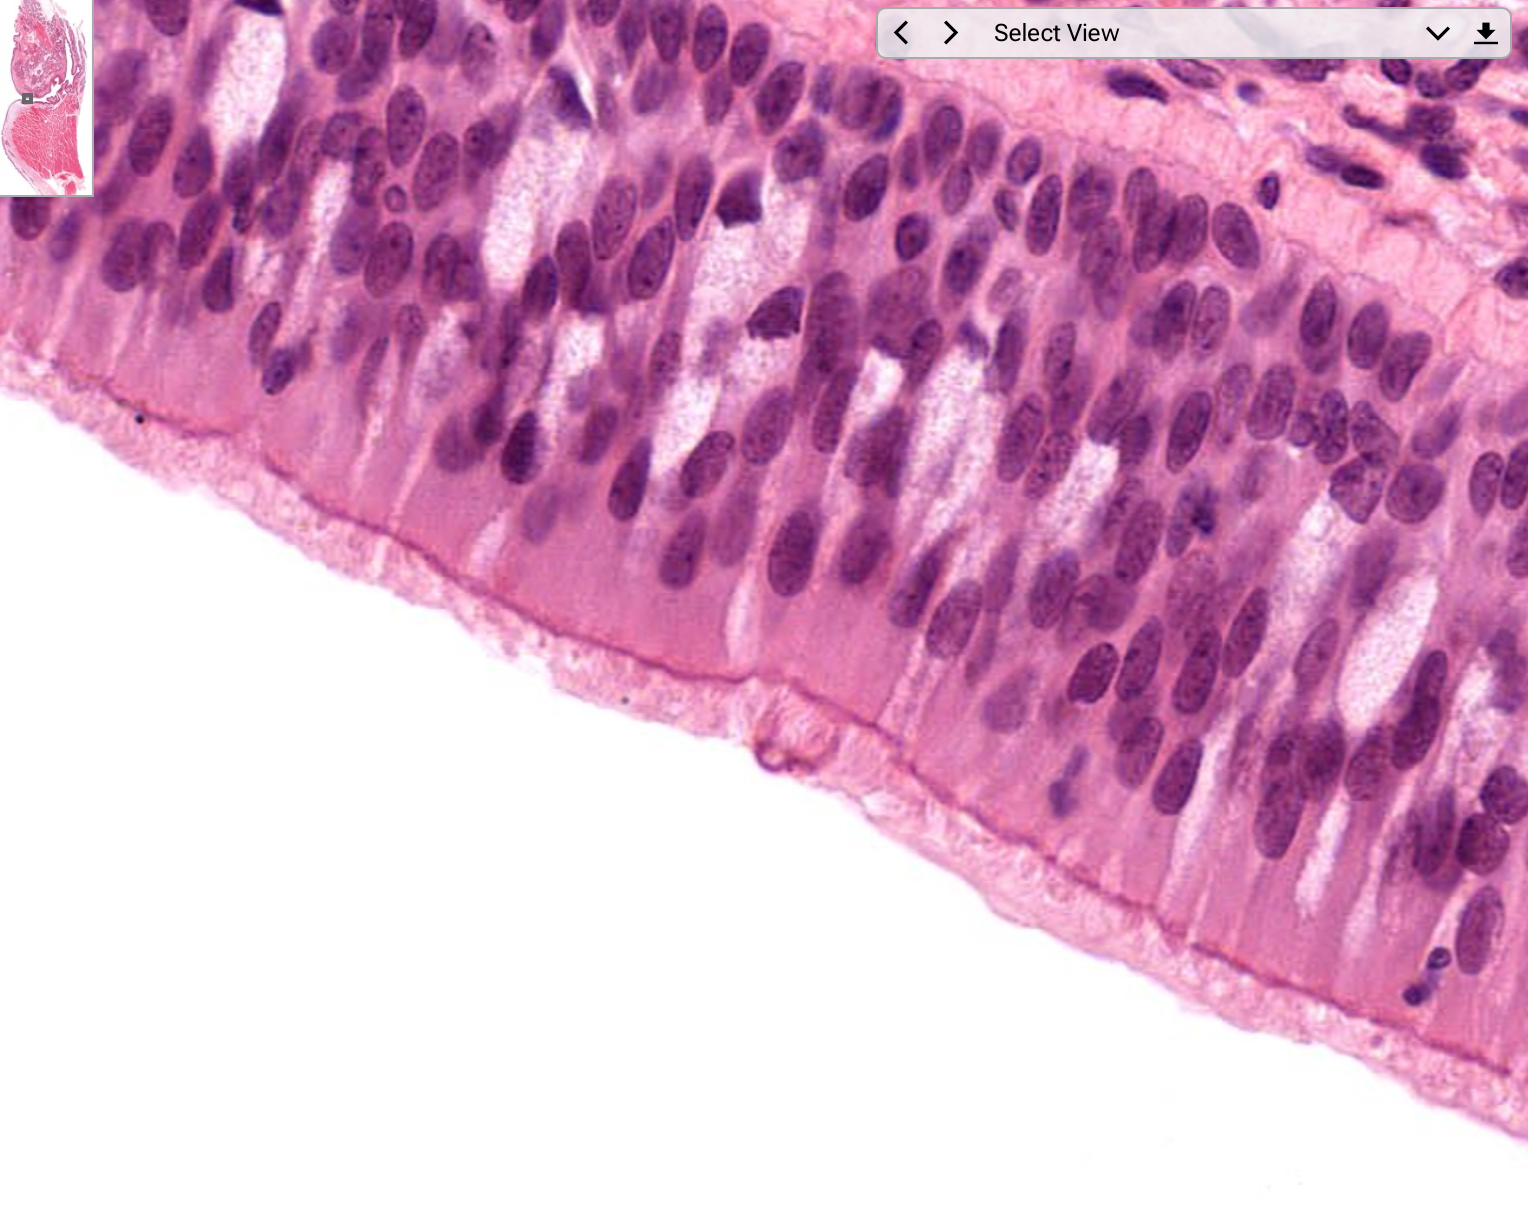

Tissue: pseudostratified columnar epithelium

Location: larynx

Function:

• secretion of mucus

• ciliated: propel mucus by ciliary action